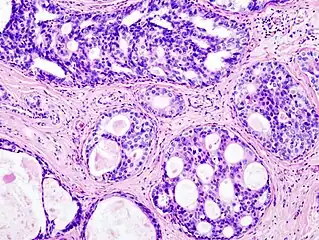

Ductal carcinoma in situ (DCIS) in breast tissue, cell nuclei (blue-purple), extracellular material (pink)